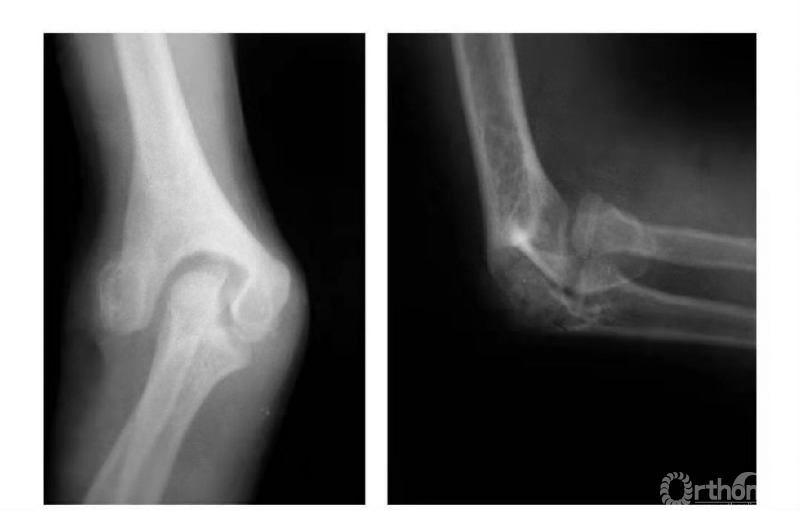

例5:肱骨内髁外侧壁骨骺因损伤而早闭,而内外侧骨骺继续生长致滑车沟变深,继而肱骨下端形成鱼尾状畸形(图8)。

图8